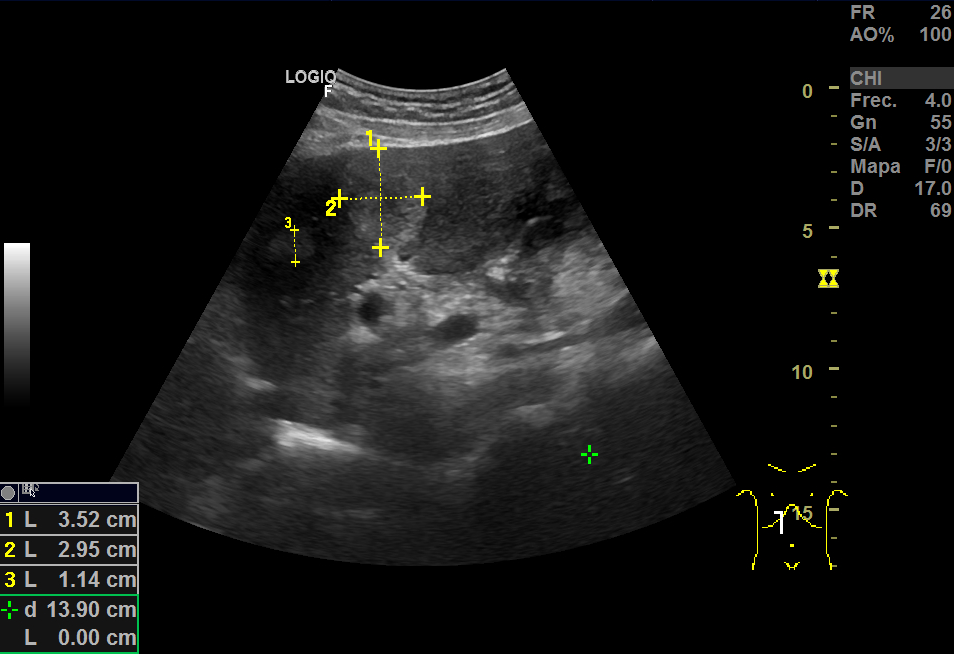

En la ecografía, a nivel hepático, vimos unas imágenes hiperecoicas redondeadas hipervascularizadas: una de aproximadamente 5 cm de diámetro y otra de 3cm, sospechosas de LOEs (lesiones ocupantes de espacio).

Repite la ecografia: En el segmento IV, aparece una imagen redondeada de 30x40 mm heterogénea, iso-hipoecogénica sin captación ecodoppler que podría ser un angioma, HFN (hiperplasia nodular focal) u otra posibilidad; otra imagen oval hiperecogénica de 19 mm, que sugiere angioma como primera posibilidad.

TAC con contraste: Se ven al menos cuatro lesiones hipodensas, con realce centrípeto compatible con hemangioma.

Se diagnostica de hemangiomas (uno de ellos, de 4 cm).